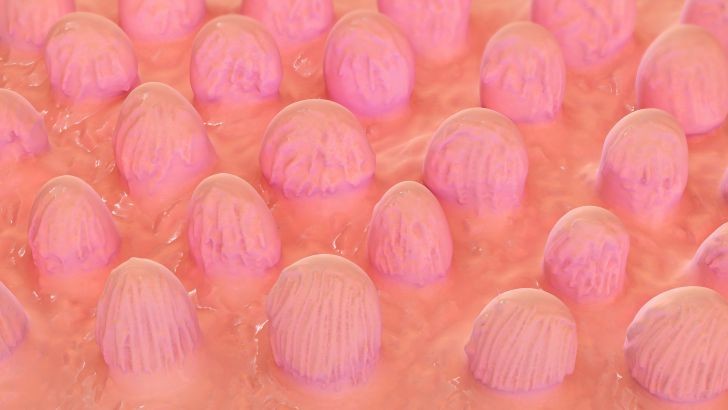

When you have a cold, why does food taste bland?

A cold increases the rate at which taste buds die and replacement taste buds are formed at a slower than usual rate.

The lack of desire to eat when ill causes food to taste bad.

Much of what we perceive as taste is actually smell.

A cold causes taste receptors to malfunction.